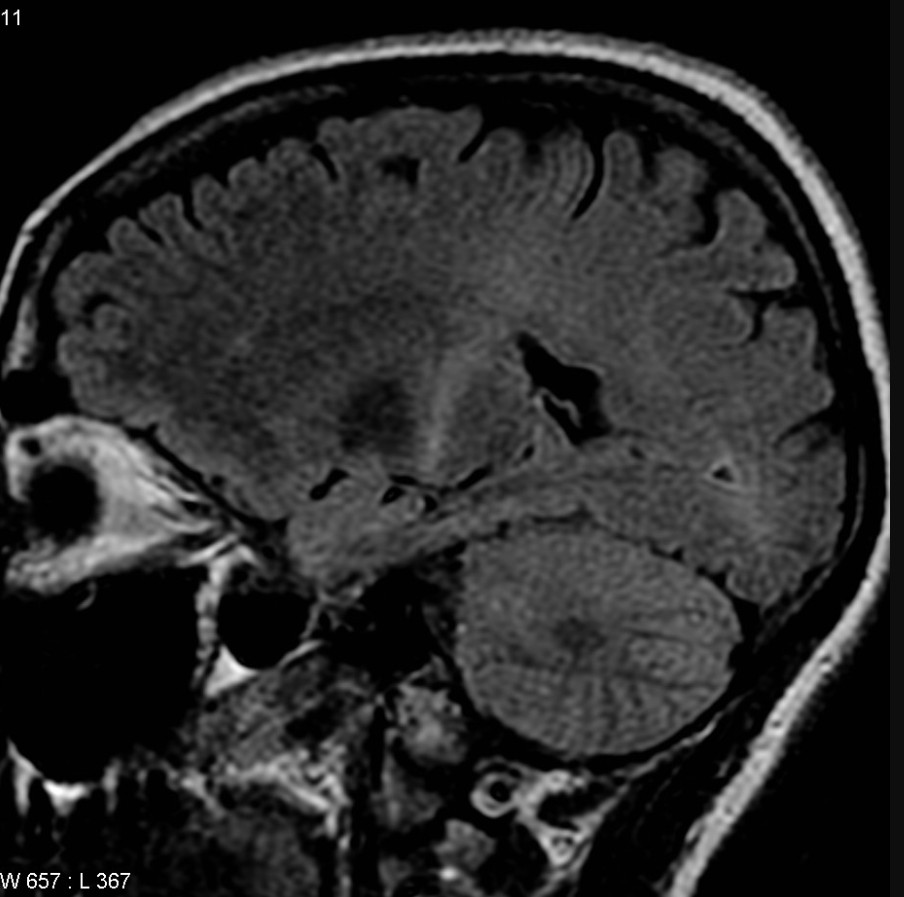

Через 35 лет тот же диагноз получил 80-летний диктатор. К тому времени версию о микробах-возбудителях всерьез уже не рассматривали, а нейродегенерацию считали одним из проявлений старения нервной системы. Было понятно, что в ткани мозга появляются какие-то бляшки — как при болезни Альцгеймера или Паркинсона — которые и вызывают прогрессирующий паралич. Именно эти бляшки, тогда еще неясной природы, за десять лет превратили бодрого старика, который и в 72 года переплывал Янцзы, — в безнадежного пациента, который мог дышать, только лежа на боку. От диагноза до смерти, как и в случае с бейсболистом, прошло около двух лет.

Британскому астрофизику повезло больше. Свой приговор он услышал еще до того, как его собрат по несчастью пересек Янцзы в последний раз, но болезнь остановилась в полушаге от летального финиша. Медленно теряя подвижность головы, ученый прожил еще 55 лет, стал иконой научпопа и новым символом своей болезни. За это время стало понятно, что агрегаты в мозге состоят из белков, у этих белков появились имена, а на горизонте замаячили возможные гены-виновники. Полсотни клинических испытаний лекарств стартовали и сошли с дистанции досрочно. Миллионы людей вылили на себя ведра ледяной воды, собирая деньги на исследование болезни. Но никто так и не понял, как ее лечить.

Боковой амиотрофический склероз (БАС), который погубил Лу Герига, Мао Цзэдуна и Стивена Хокинга — лишь одно из множества нейродегенеративных заболеваний, против которых человечество до сих пор бессильно. И хотя далеко не всегда БАС заканчивается деменцией, с болезнями Альцгеймера и Паркинсона его сравнивали не зря. Препятствия, которые отделяют нас от лекарства, во всех этих случаях примерно одни и те же: предсказать болезнь невозможно, диагностировать на ранних стадиях удается не всегда, причины многоообразны, а список их не полон.